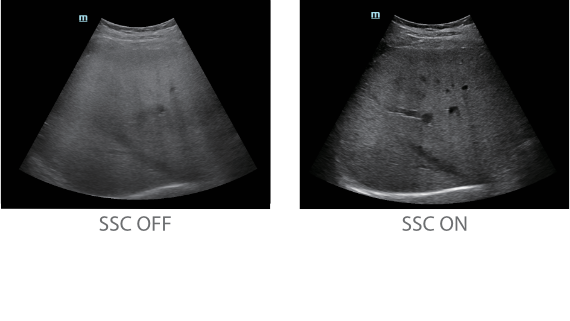

Dank der ZONE Sonography?-Technologie (ZST+) wird das B-Bild des Resona 7 ├╝ber die komplette Tiefe fokussiert, sodass keine Fokuspunkte mehr gesetzt werden m├╝ssen. Die Schall-Lauf-Geschwindigkeit (SSC) wird auf Knopfdruck individuell auf den Patienten angepasst, was die Darstellung von Organen, Grenzfl?chen und Gewebever?nderungen erheblich verbessert. Und dank der fortschrittlichen iFusion-Funktion k?nnen optional die Daten von Ultraschall-, MRT-und CT-Bildern synchronisiert werden.